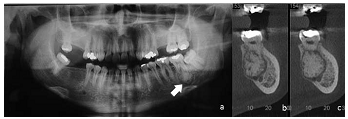

Homem de vinte e cinco anos de idade, melanoderma, compareceu a unidade odontológica para a remoção de terceiro molar superior. Por imagem radiográfica, constatou-se aumento de volume radiopaco fundido ao ápice do dente 37 circundado por um fino halo radiolúcido, conforme indicado pela seta na imagem radiográfica a. Foi solicitada a realização de tomografia, para confirmação das características previamente identificadas. As imagens da tomografia correspondem às indicadas pelas letras b e c.